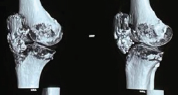

A 41-year-old lady presented to the OPD with complaints of swelling and progressive pain over the right inguinal region for the past 7 years. The swelling was initially small and gradually progressed to attain the present size. The swelling was associated with rest pain, and the pain was exacerbated during physical activity like walking or climbing stairs. No history of trauma to the region. There was no history of weight loss or loss of appetite. The patient was self-medicating with NSAIDs for pain relief. Clinical examination revealed a gross bony hard swelling over the right inguinal region. The swelling was non-tender. There were no sinuses or discharge. There was a restriction in the range of motion (ROM) at the hip joint with flexion of 20°, abduction was nil, internal rotation of 10°, external rotation of 20°, and extension of 10°. Further examination revealed an abduction contracture of 20° with anterior joint line tenderness. There were no similar swellings elsewhere in the body. The initial baseline investigations were within normal limits. The plain radiograph of the pelvis with both hip joints revealed a metaphyseal-diaphyseal swelling over the medial aspect of the right proximal femur adjacent to the lesser trochanter, with loss of sphericity of the femoral head, joint space narrowing, and osteophyte formation. The cortex appeared to be continuous with the femoral cortex, and the matrix was homogenous with patchy areas of mineralization (Fig. 1).

The magnetic resonance imaging (MRI) revealed an expansile lesion with no associated soft-tissue component. Pre-operative angiography was done to confirm perfusion of the deep branch of the medial femoral circumflex artery and to detect eventual alteration of its normal course cranial to the lesser trochanter and dorsal to the greater trochanter. The provisional diagnosis of sessile solitary osteochondroma with probable sarcomatous degeneration and secondary hip osteoarthritis (OA) was considered after radiographic evaluation. The patient was explained about the possibility of sarcomatous degeneration of the tumor, considering its longer duration of symptoms and the presence of rest pain. Under general anesthesia, the patient was placed in a left lateral position. Through the posterior approach, the proximal femur was exposed, retaining the short external rotators with a sleeve of cortical bone. The tumor was found to be involving the medial and posterior cortex of the proximal femur. The femoral head was dislocated posteriorly after performing a capsulotomy. Wide excision of the tumor by excision of the entire proximal femur was performed to remove the osseous base to avoid any chances of recurrence (Fig. 2). Diaphysis was reamed according to pre-operative templating. Serial reaming of the acetabulum was done, followed by the implantation of a cemented acetabular cup. A distally inter-locked modular Hydroxy apatite-coated femoral reconstruction prosthesis (REEFTM, Depuy) was used on the femoral side (Fig. 3). Intraoperative samples were sent for histopathological examination.